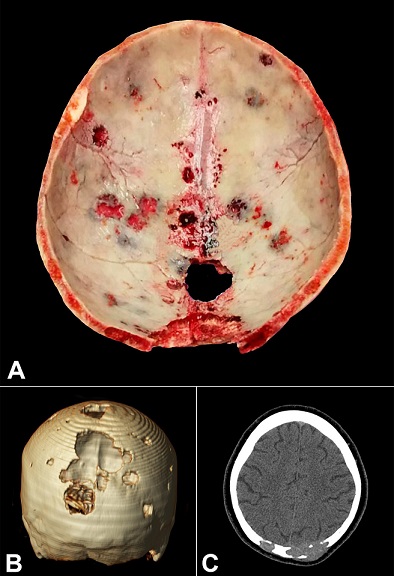

“Punched out” multiple myeloma lytic lesions in the skull

Figure 1 refers to the case of a 62-year-old woman who presented headache, fatigue, weight loss, episodes of blurred vision and diplopia, bone pain, and the appearance of numerous nodules in the scalp. The laboratory work-up revealed hypercalcemia, azotemia, multiple lytic bone lesions (skull, sternum, ribs, vertebrae, ilium), and urinary kappa Bence-Jones protein. The bone marrow biopsy showed infiltration of atypical plasma cells, with monoclonal expression of κ-light chain. The patient died due to a sudden cardiac arrest, which the autopsy revealed to be caused by a massive pulmonary embolism.